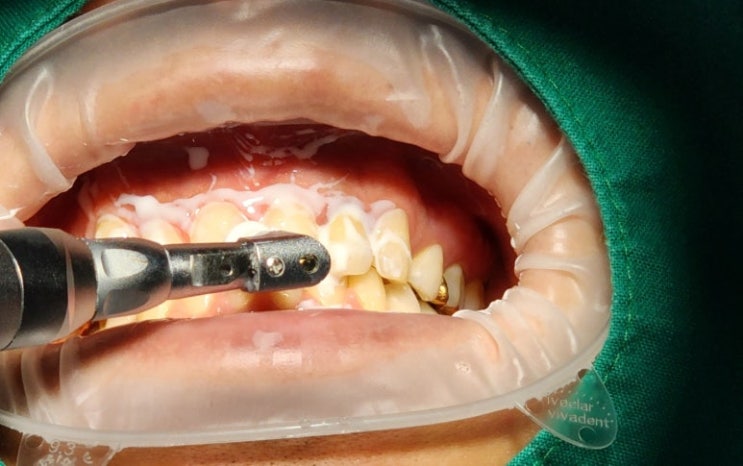

인천대입구역 치과 '아파프로(APAPRO)'를 동반한 안전한 전문가 원데이 치아미백

반갑습니다. 인천대입구역 치과 리봄의 박현호 원장입니다. 하루 만에 하얀 치아를 가질 수 있다는 장점 덕...